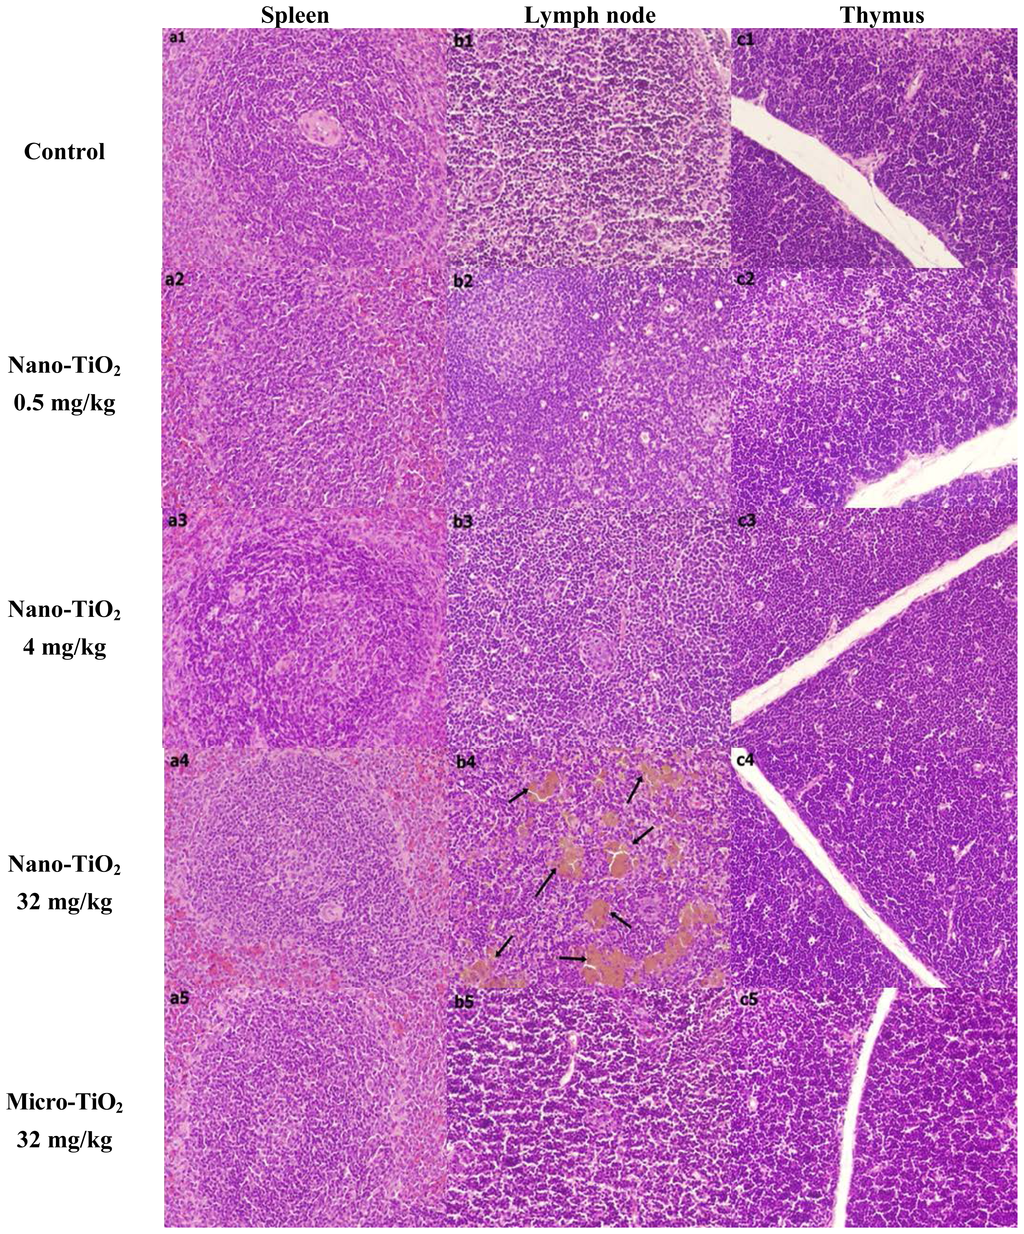

2.1. Histopathological Examination

4.3. Histopathological Examination